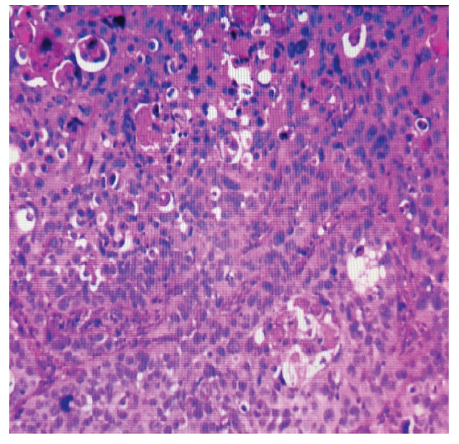

妊娠合并宫颈癌一例

Pregnancy with Cervical Cancer: A Case Report

妊娠合并宫颈癌较为罕见,早期临床表现并不典型。由于缺乏妇科肿瘤筛查意识,易与胎膜早破、先兆早产等疾病相混淆,导致治疗延误。妊娠合并宫颈癌的治疗尚无成熟且规范的方案,尤其是妊娠中期宫颈癌的治疗存在很大争议,需要根据病理检查、分期、胎儿发育情况及孕妇的妊娠期望等制定个体化综合治疗方案。回顾性分析1例以阴道流血流液入院,经保守治疗失败后,行剖宫产术终止妊娠的中期妊娠合并宫颈癌的诊治经过,并对相关文献进行复习,以期为疾病的诊治提供经验。

Pregnancy with cervical cancer is relatively rare, early clinical manifestations are not typical. Due to the lack of awareness of gynecological tumor screening, it is easy to be confused with premature rupture of membranes, threatened premature delivery and other diseases, lead to treatment delay. There is no mature and standardized treatment for cervical cancer in pregnancy, especially the treatment of cervical cancer in the mid trimester of pregnancy is controversial. It is necessary to formulate individualized comprehensive treatment plan according to disease examination, staging, fetal development and pregnant women′s pregnancy expectation. This is a retrospective analysis of a case of second trimester pregnancy with cervical cancer who was admitted to the hospital with vaginal bleeding, after failure of conservative treatment, cesarean section was performed to terminate the pregnancy. We report this case and review the relevant literature, hoping to provide experience for the diagnosis and treatment of the disease.